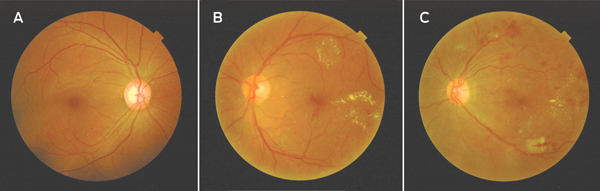

1 Fundus photographs (examples from study cohort) showing a normal fundus (A), clinically significant macular oedema (B) and proliferative diabetic retinopathy (C)

All participants underwent detailed ocular examination. Baseline acuity was measured using a tumbling E acuity chart at 3 metres in a well lit room. An optometrist performed subjective refraction and determined refracted visual acuity. The optometrist performed a slit lamp examination of the anterior segment, followed by pupil examination using a hand torch. After an assessment of anterior chamber depth, the pupils were dilated using tropicamide 1.0% and phenylephrine 2.5% solution. The visiting ophthalmologist (T H) performed stereoscopic slit-lamp fundoscopy using a 90-dioptre fundoscopy lens. The presence and degree of DR was graded using the Early Treatment of Diabetic Retinopathy Study (ETDRS) adaptation of the modified Airlie House classification of DR12 by clinical comparison with standardised photographs (Box 1). The DR was graded as either no DR (level 10–13), minimal non-proliferative DR (NPDR) (level 14–19), mild NPDR (level 20–39), moderate NPDR (level 40–49), severe NPDR (level 50–59) and proliferative DR (PDR) (level 60–85). Clinically significant macular oedema (CSMO) was defined as any retinal thickening within 500 µm of the fovea associated with retinal thickening that is at least one disc area in size within one disc diameter of the fovea.